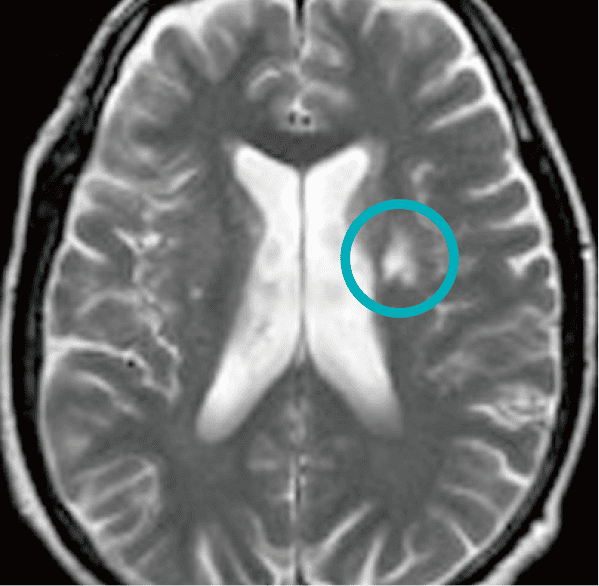

慢性虚血性変化

年をとると顔にシワやシミができるのと同じように、脳も少し萎んだり、シミができたりしますが、脳のシミが少し目立っている状態です。進行すると脳卒中の危険因子になると考えられています(危険比率2.0〜2.7倍)。これ自体を治療することはできません。背景に高血圧など他の病気が隠れていることもありますので、健診で指摘された他の問題点について、改善するように努めてください。病変の程度によっては経過観察が必要になります。万一症状が出現した際は、直ちに医療機関を受診してください。